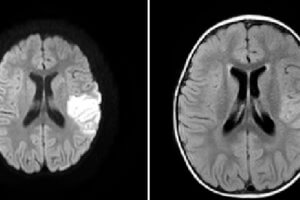

Middle Cerebral Artery Territory Infarct

The middle cerebral artery is the major supplier of blood to the cerebral cortex. It consists of 4 principal segments, M1-M4. M1 refers to the horizontal course of the artery from its... Read more »

Acute infarcts lead to cell swelling in a process called cytotoxic edema. Signal in diffusion weighted MRI (DWI) is inversely related to the degree of brownian motion of intraparenchymal water. When an... Read more »